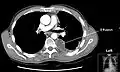

La TAC se utilizará en caso de que exista patología pulmonar asociada o cuando se requiera definir mejor la localización anterior o posterior del proceso. También será útil para diferenciar una lesión pleural de una lesión en el parénquima pulmonar.

Masivo derrame pleural izquierdo (zona blanca) en un paciente con cáncer de pulmón. -

TAC TAC de tórax con derrame pleural izquierdo. -